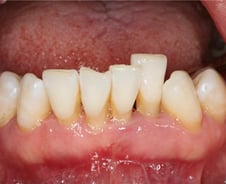

#. 50대 A씨는 요즘 양치할 때나 거울을 볼 때마다 시름이 깊다. 바로 눈에 띄게 내려앉은 잇몸 때문. 드러난 치아 뿌리 때문에 양치질할 때 바늘로 찌르는 듯한 통증과 시린 증상이 밀려온다. 게다가 웃거나 말할 때마다 내려앉은 잇몸이 노출되는 탓에, 사람들의 시선이 느껴지는 것 같아 심리적으로 위축된다. A씨처럼 잇몸 조직이 소실되며 치아 뿌리 방향으로 치아와 치은 부착 부위가 이동하는 현상을 '치은퇴축'이라고 한다. 한 번 내려앉은 잇몸은 심미적 문제 외에도 통증을 동반할 수 있다. 치은퇴축이 발생하는 대표적인 요인은 불량한 구강위생으로 인한 치주질환이다. 치아와 잇몸 사이 틈새인 '치은열구' 내에 세균성 치태가 쌓이면서 잇몸 염증이 생기기 시작하는데, 이때 하방의 치조골(잇몸뼈)을 녹이면서 잇몸도 따라 내려간다. 관악서울대치과병원 김윤정(치주과 전문의) 교수는 "지나치게 단단한 칫솔모를 사용해 과도한 칫솔질을 하는 것, 이갈이 등의 악습관도 잇몸 퇴축을 촉진할 수 있다"며 "